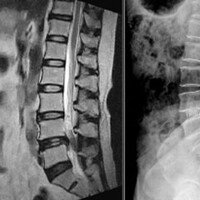

간단 수술 척추관 넓히니 앉은뱅이가 벌떡?

허리가 아프면 ‘디스크(추간판탈출증)’를 의심하는 경우가 많다. 디스크만큼 흔하진 않지만 요통의 큰 원인 중 하나는 ‘척추관 협착증’이다. 허리가 아프고 다리가 저린 증상 때문에 디스크로 오인되기 쉽지만, 환자가 호소하는 증상만으로…